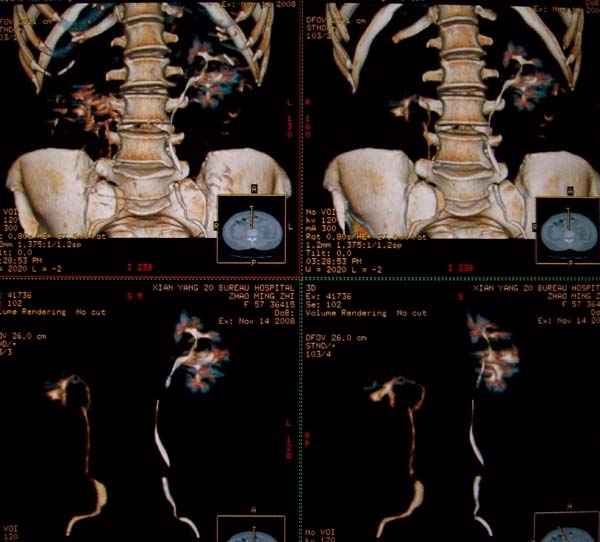

以下是引用dr.yang在2008-11-9 21:56:00的发言:[br]右肾上极占位?建议增强

以下是引用x-man在2008-11-9 22:30:00的发言:[br]建议先增强,右肾影明显增大,上极见边不清低密度肿块影,肿瘤待定.

以下是引用卜一在2008-11-10 8:09:00的发言:[br]建议先增强,右肾影明显增大,上极见边不清低密度肿块影,肿瘤待定.支持!另:第一次碎石是否肾受到损伤?合并感染?不知第一次碎石前是否做过彩超?

以下是引用dsl555在2008-11-9 23:57:00的发言:[br]建议先增强,右肾影明显增大,上极见边不清低密度肿块影,肿瘤待定. [br] [br]